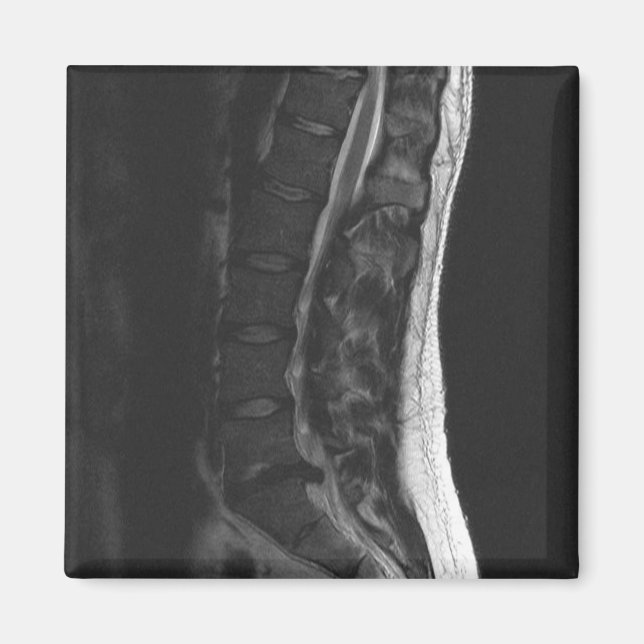

Imán de disco retorcido

¡Convirtí mi resonancia magnética en un imán de refrigerador! Muestra mi disco L5-S1 que se ha roto. ¡Siempre me recordará usar la postura apropiada y doblarme de rodillas! No dejes que esto te pase... he tenido dos cirugías para corregirlo.